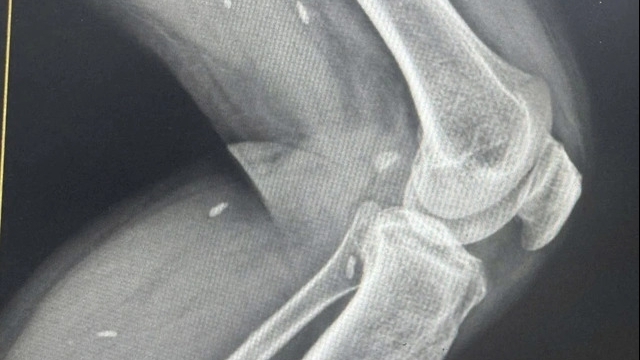

| Nhiều bệnh nhân đến bệnh viện trong tình trạng đột quỵ nặng do chủ quan không kiểm tra sức khỏe thường xuyên để phát hiện bệnh lý nền. |